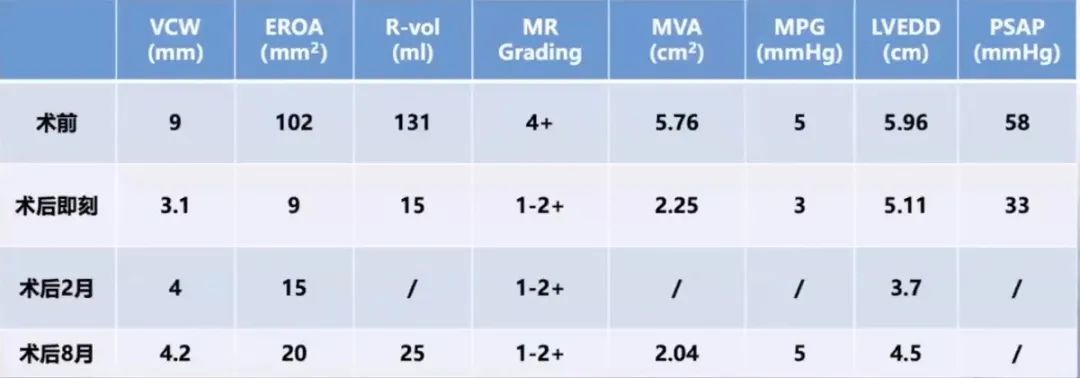

患者女性,76岁,主诉活动后出现胸闷气促1月。既往有原发性高血压病史。诊断为退行性二尖瓣反流(DMR),Carpentier分型为Ⅰ型,基础二尖瓣反流程度达5+,属极重度反流。超声心动图评估显示左心房明显扩大,左心室舒张末期内径(LVEDD)为6.0cm,左心室射血分数(LVEF)为72%。肺动脉收缩压(PASP)升高至58mmHg,提示合并肺动脉高压,三尖瓣反流为轻至中度。

进一步评估患者病变情况,前叶长度2.74mm,后叶长度1.93mm;房间隔前后径4.0cm,房间隔长径6.9cm,瓣口面积6.27cm²,平均跨瓣压差5mmHg。

术后转归及随访

术前可见肺静脉逆流,术后则消失,反流明显改善。跨瓣压差由术前的19mmHg降至术后8mmHg,瓣膜血流动力学明显优化。同时,LVEDD由术前的6cm逐渐降至<5.0cm,患者左心室容量负荷减轻,心腔重构趋势明确,手术取得良好近期疗效。